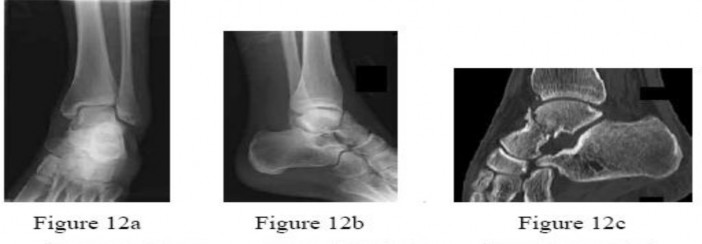

ORTHOPEDIC MCQS ONLINE 015FOOT and Ankle CLINICAL SITUATION FOR QUESTIONS 1 THROUGH 4 A B Figures 1a and 1b a…